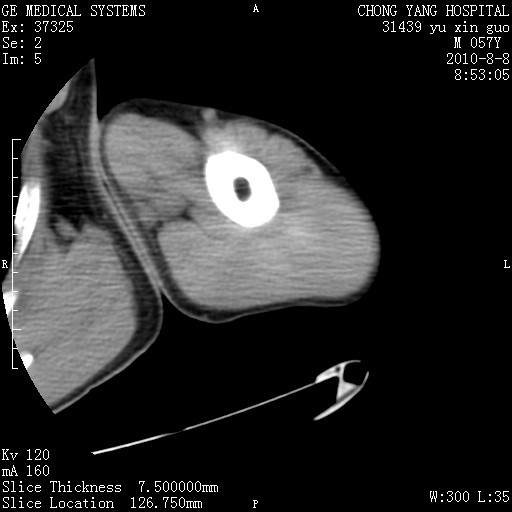

标题: CT28267:M57Y 上臂包块8年余。 [打印本页]

标题: CT28267:M57Y 上臂包块8年余。

典型脂肪瘤改变

上臂软组织内脂肪瘤。

包膜光滑、完整的脂肪密度肿块,支持脂肪瘤。